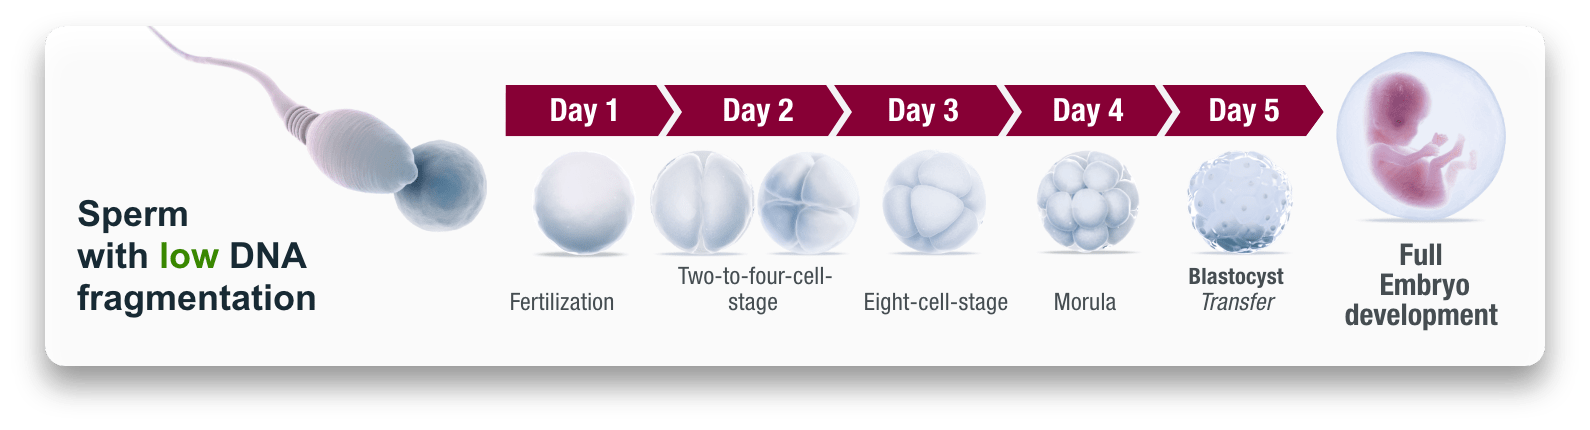

HOW SPERM PRODUCTION WORKS

Hormones play a decisive role in sperm production (=spermatogenesis). The pituitary gland generates a hormone known as follicle stimulating hormone (FSH). The luteinizing hormone (LH) is generated at the same time. While both hormones lead to the maturation of egg cells in women, in men they are responsible for the formation of sperm cells.

Therefore, sperm count can vary person-to-person. The average, sexually mature man has about two to 3 billion sperm available at any given time. But because sperm cells in the seminiferous tubules are constantly being regenerated, these reserves are always a mixed bag of sperm cells at different stages of maturity.

BENEFITS OF 360 FERTILITY BOOSTER

- Improves all sperm parameters necessary for successful conception and pregnancy

- Significant improvement in motility, morphology, sperm volume and sperm count

- Significant reduction of DNA fragmentation(Miscarriage) in sperm cells

- Supports the recovery of sperm quality